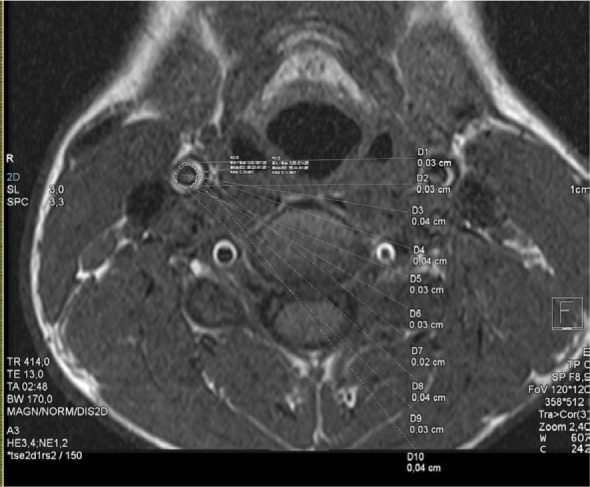

Background: Epicardial adipose tissue (EAT) is a biologically active visceral brown adipose tissue, which is irregularly distributed across myocardium. It has emerged as a potential modifiable cardiometabolic biomarker in adults, demonstrating pro-inflammatory properties with involvement in subclinical atherosclerosis. The increased thickness of the inner two layers of the carotid artery wall (intima and media) in childhood can pose as a risk of the development of atherosclerotic disease and its complications in adult life, representing additional potential biomarker. The purpose of our study was to evaluate a relation between EAT volume (EATV) and carotid intima-media thickness (cIMT) in children and adolescents who have been diagnosed with primary arterial hypertension (AH), utilizing magnetic resonance imaging (MRI).

Patients and methods: The study included 72 children and adolescents, half of them had an established diagnosis of primary AH and the other half were matched healthy controls. The EATV and cIMT measurements were compared between the two groups and correlated with clinical, anthropometric and functional parameters.

Results: Children diagnosed with AH exhibited a significantly higher EATV (16.5 ± 1.9 cm3 vs. 10.9 ± 1.5 cm3; t = -13.815, p < 0.001) and higher cIMT (0.7 [0.2] mm vs. (0.4 [0.1) mm]; U = 54, p < 0.001) compared with their healthy counterparts. EATV demonstrated a significant correlation with cIMT.

Conclusions: Increased EATV and cIMT were found with MRI in hypertensive children compared to their healthy counterparts. EATV demonstrated a stronger association with hypertension than cIMT. EATV emerged as an independent predictor of cIMT.